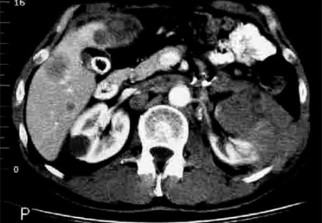

L’incidence du cancer du rein est en constante augmentation en Algérie où quelque 53.000 cas sont répertoriés, ont souligné, mercredi à Oran, les participants aux 1ères journées internationales d’onco-urologie sur le thème "Cancer du rein : actualités et perspectives" .

Les interventions des participants à cette première rencontre du genre, ont porté sur l’actualité de la prise en charge du cancer du rein en Algérie, "un cancer relativement peu fréquent en Algérie, au Maghreb, au Moyen-Orient et en Afrique, mais très fréquent en Europe et en Amérique du Nord", a souligné le Pr Blaha Larbaoui du Centre Anti-Cancer "Emir Abdelkader" de Misserghine (Oran).

Il a ajouté que "l'incidence se situe entre 2 et 2.5 pour 100. 000 habitants, ce qui correspond à environ 800 à 1.000 nouveaux cas en Algérie par an".

"Diagnostiqué tôt, le traitement du cancer du rein repose essentiellement sur la chirurgie, avec des chances de guérison pouvant atteindre les 100% ", a indiqué le Pr Larbaoui, soulignant qu’à un stade avancé, le traitement est pluridisciplinaire et reposant surtout sur la thérapie ciblée et très récemment sur l'immunothérapie.